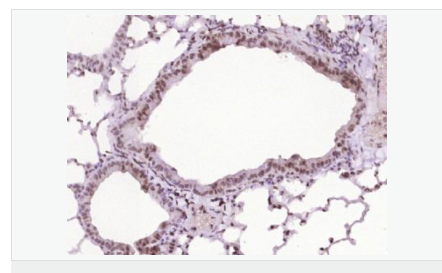

交叉反應:Human,Mouse(predicted:Rat,Pig,Cow,Horse,Rabbit) 推薦應用:IHC-P,IHC-F,IF,Flow-Cyt,ELISA

| 產品應用 | ELISA=1:5000-10000 IHC-P=1:100-500 IHC-F=1:100-500 Flow-Cyt=1ug/test ICC=1:100-500 IF=1:100-500 (石蠟切片需做抗原修復) not yet tested in other applications. optimal dilutions/concentrations should be determined by the end user. |